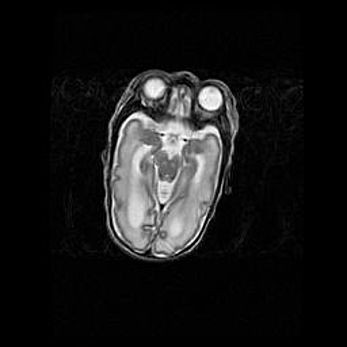

Множественные кисты обоих полушарий головного мозга, наибольшая из них в правой затылочной области. Ассиметричная атрофическая гидроцефалия.

Возраст: 7 месяцев

Вес: 5660 г

Пол: мужской

Окружность головы: 41,5 см

Срок гестации: 28-29 недель

Кисты головного мозга развиваются в результате многоочаговых некрозов вещества мозга и возникают вследствие перенесенной перинатальной инфекции, менингитов, энцефалитов, асфиксии, родовой травмы, расстройств мозгового кровообращения различного генеза. Образованию кист в веществе головного мозга плодов и новорожденных способствуют такие факторы, как высокое содержание в нем воды, недостаточная (или отсутствие) миелинизация и слабая астроглиальная реакция на повреждение.

Кисты могут сочетаться с гидроцефалией и другими поражениями головного мозга.